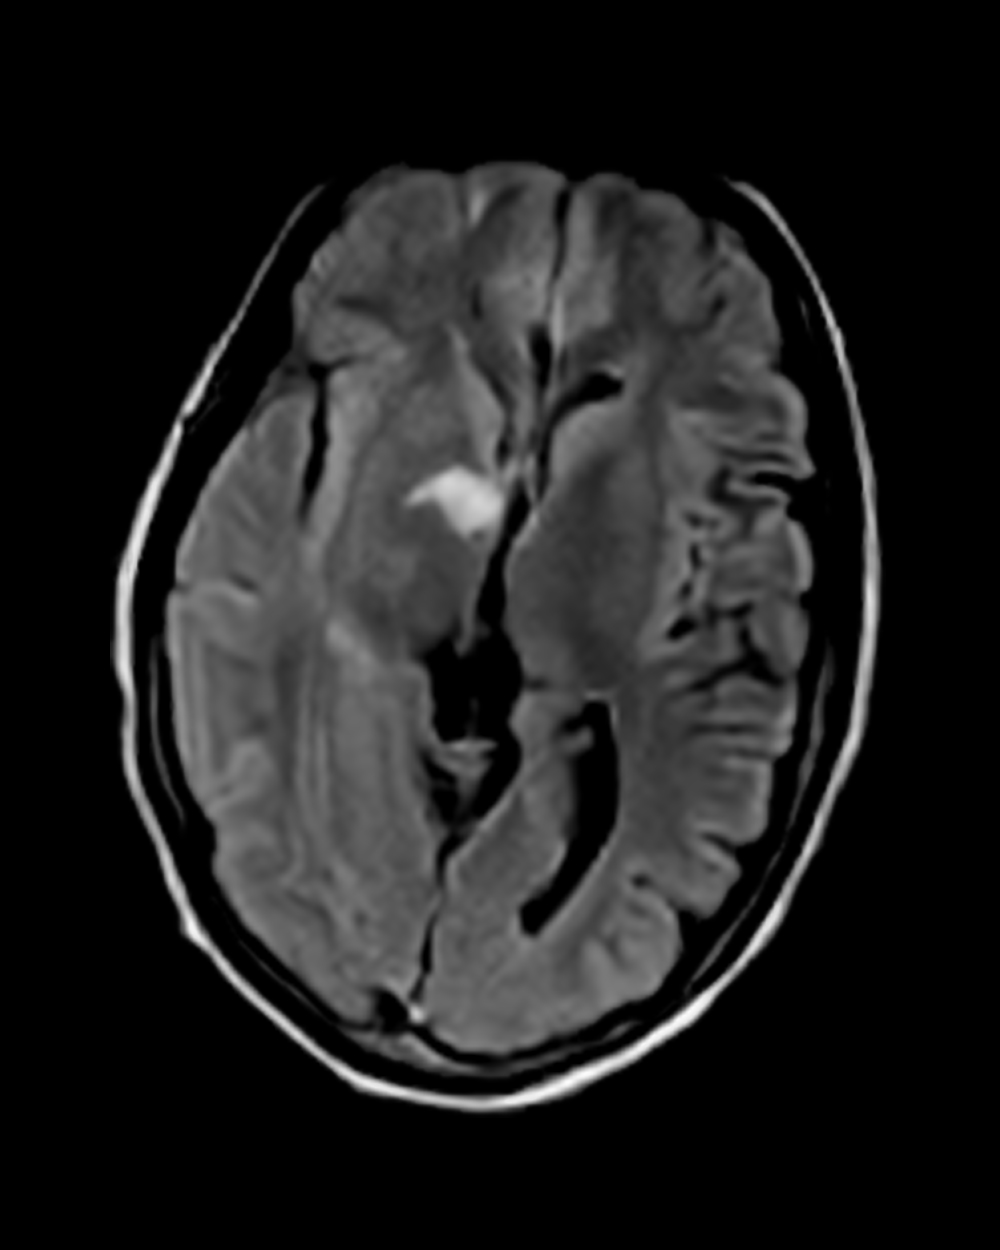

Right Anterior Choroidal Infarct

Patient Profile

63-year-old patient with a history of diabetes and hypertension. Presented to the ED with acute-onset left-sided weakness and sensory disturbance involving the face and extremities.

Portable MRI

The Swoop system was driven to the patient’s bedside and ready to scan within minutes

Stroke Detected

Swoop system images allowed clinicians to confirm infarcts

Triage

Patients were triaged to stroke units for management and monitoring